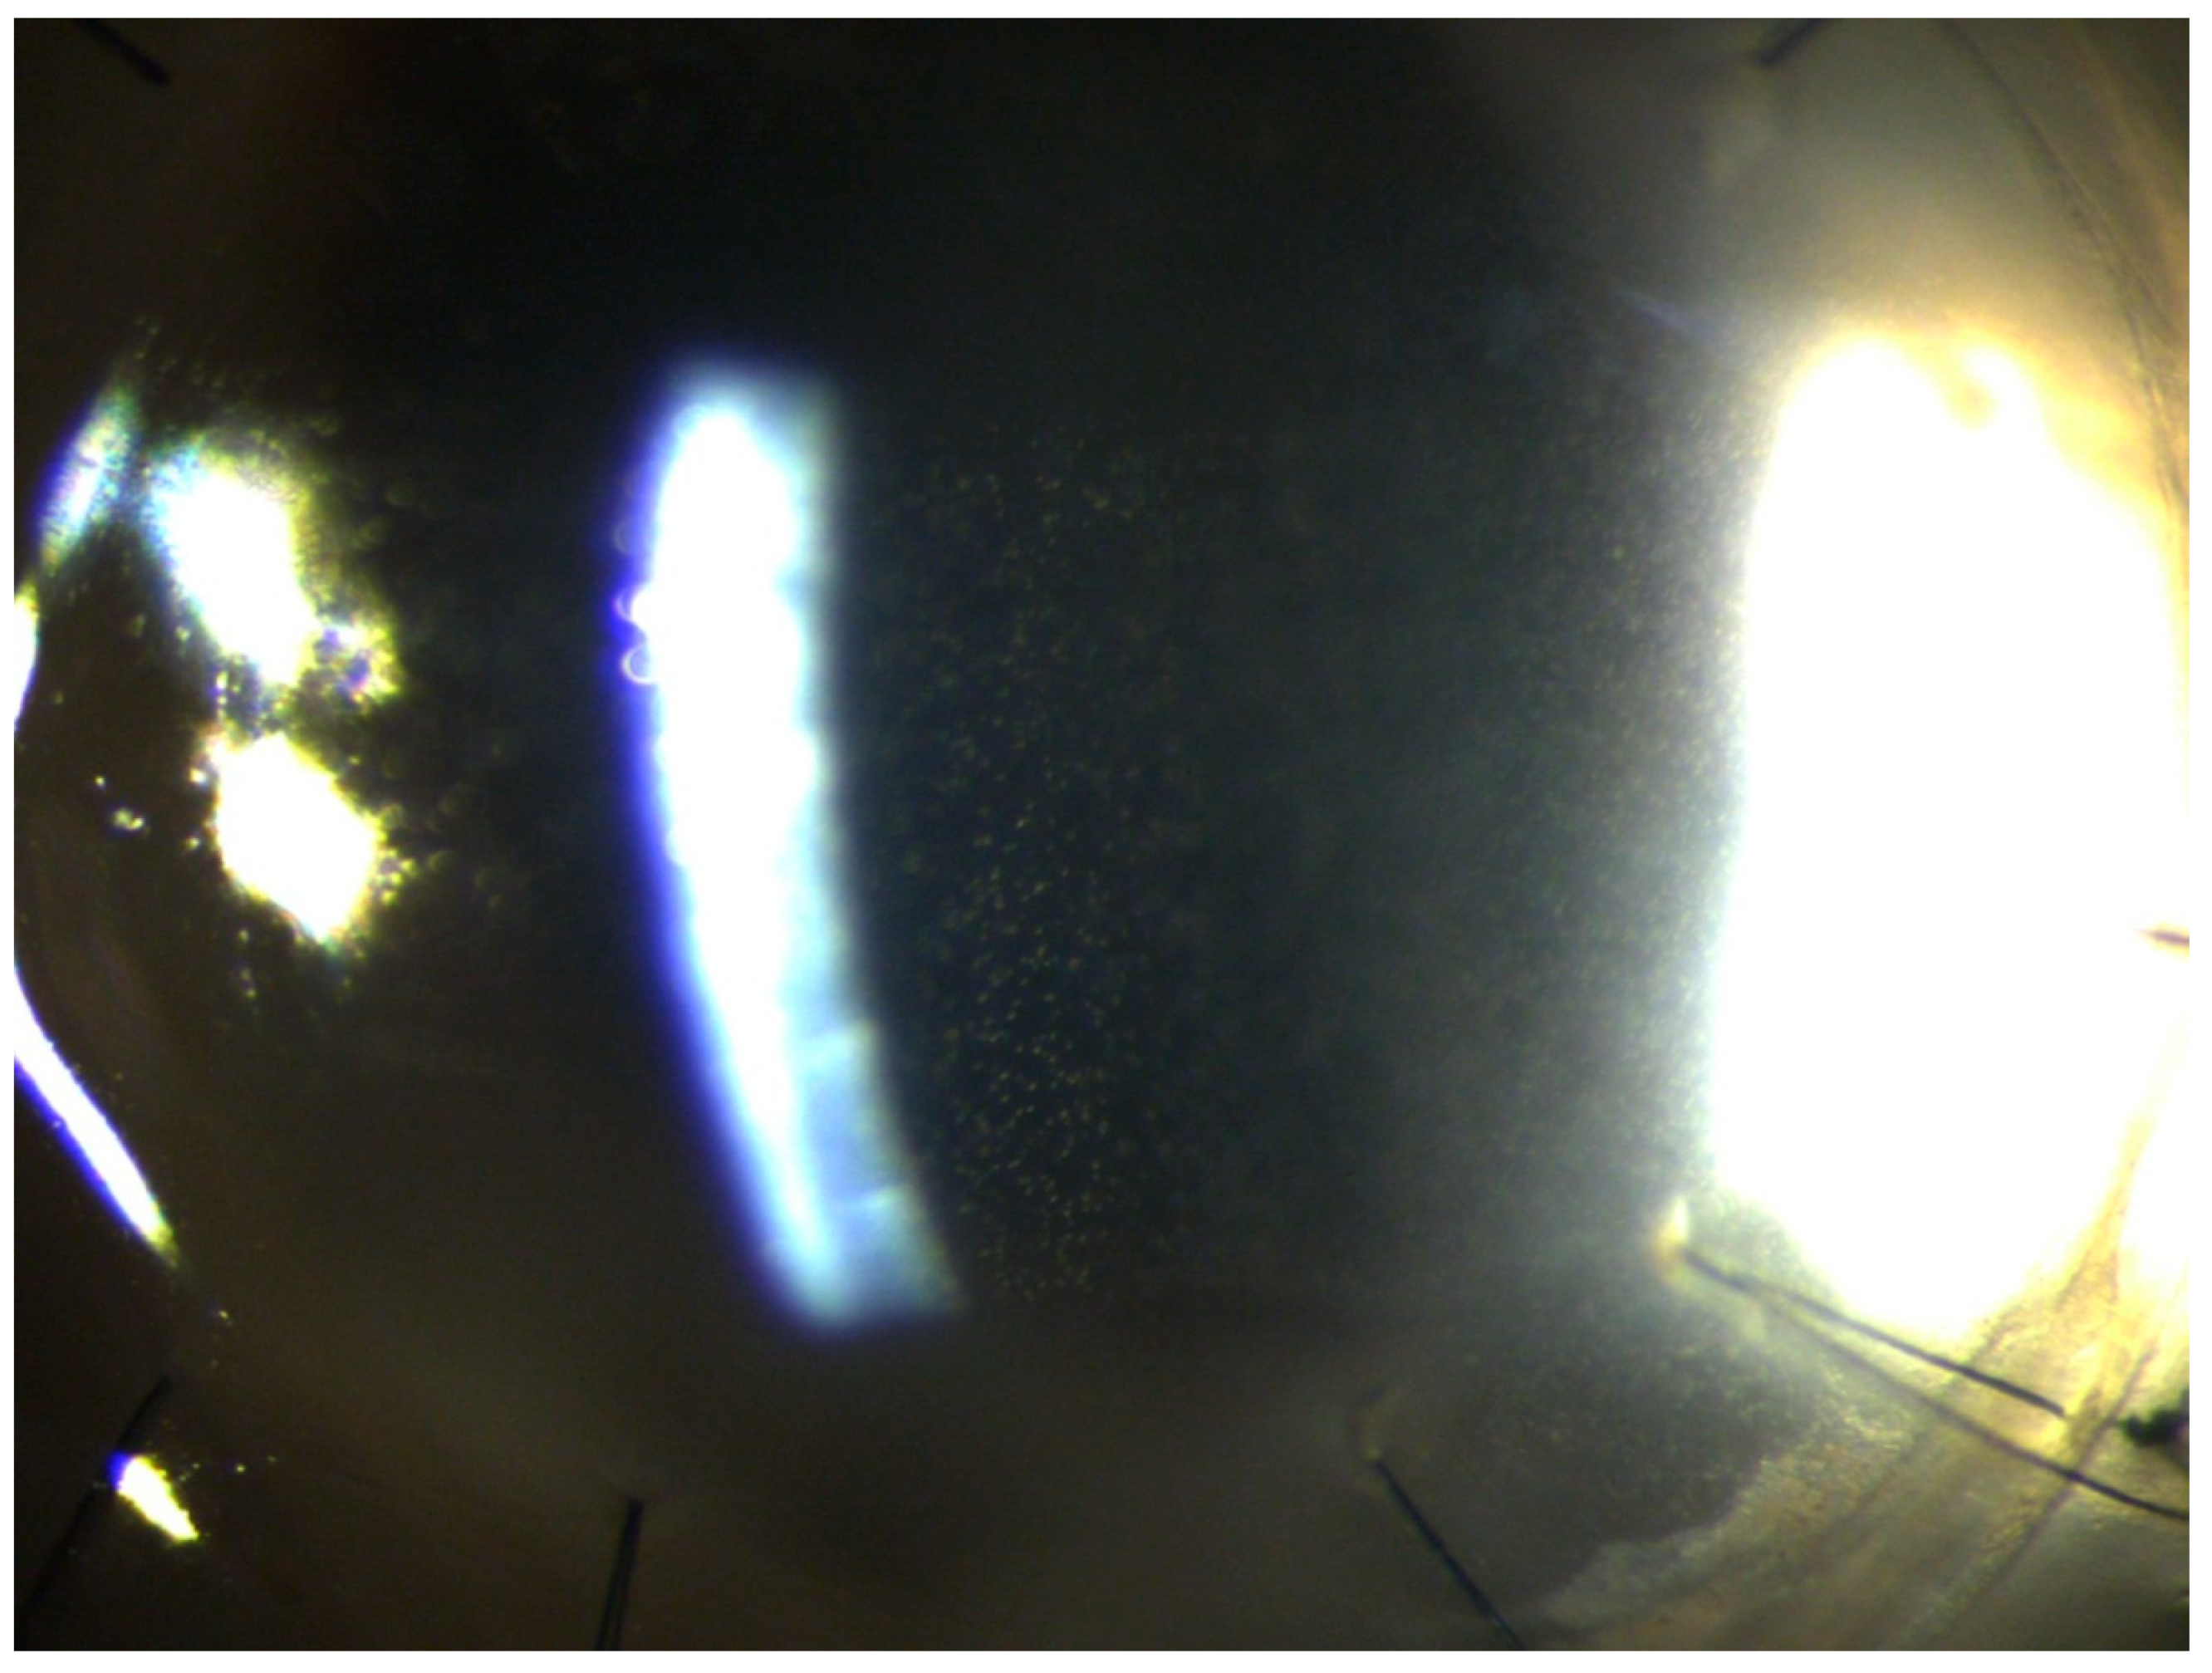

3. Results